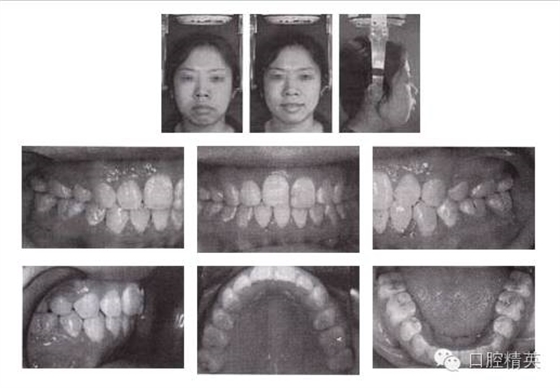

圖3-2 矯治后面像及口內(nèi)像(結(jié)束矯治 2005-04-06)

6.矯治結(jié)束后,覆頜覆蓋正常,磨牙關(guān)系達(dá)到中性,后牙直立。